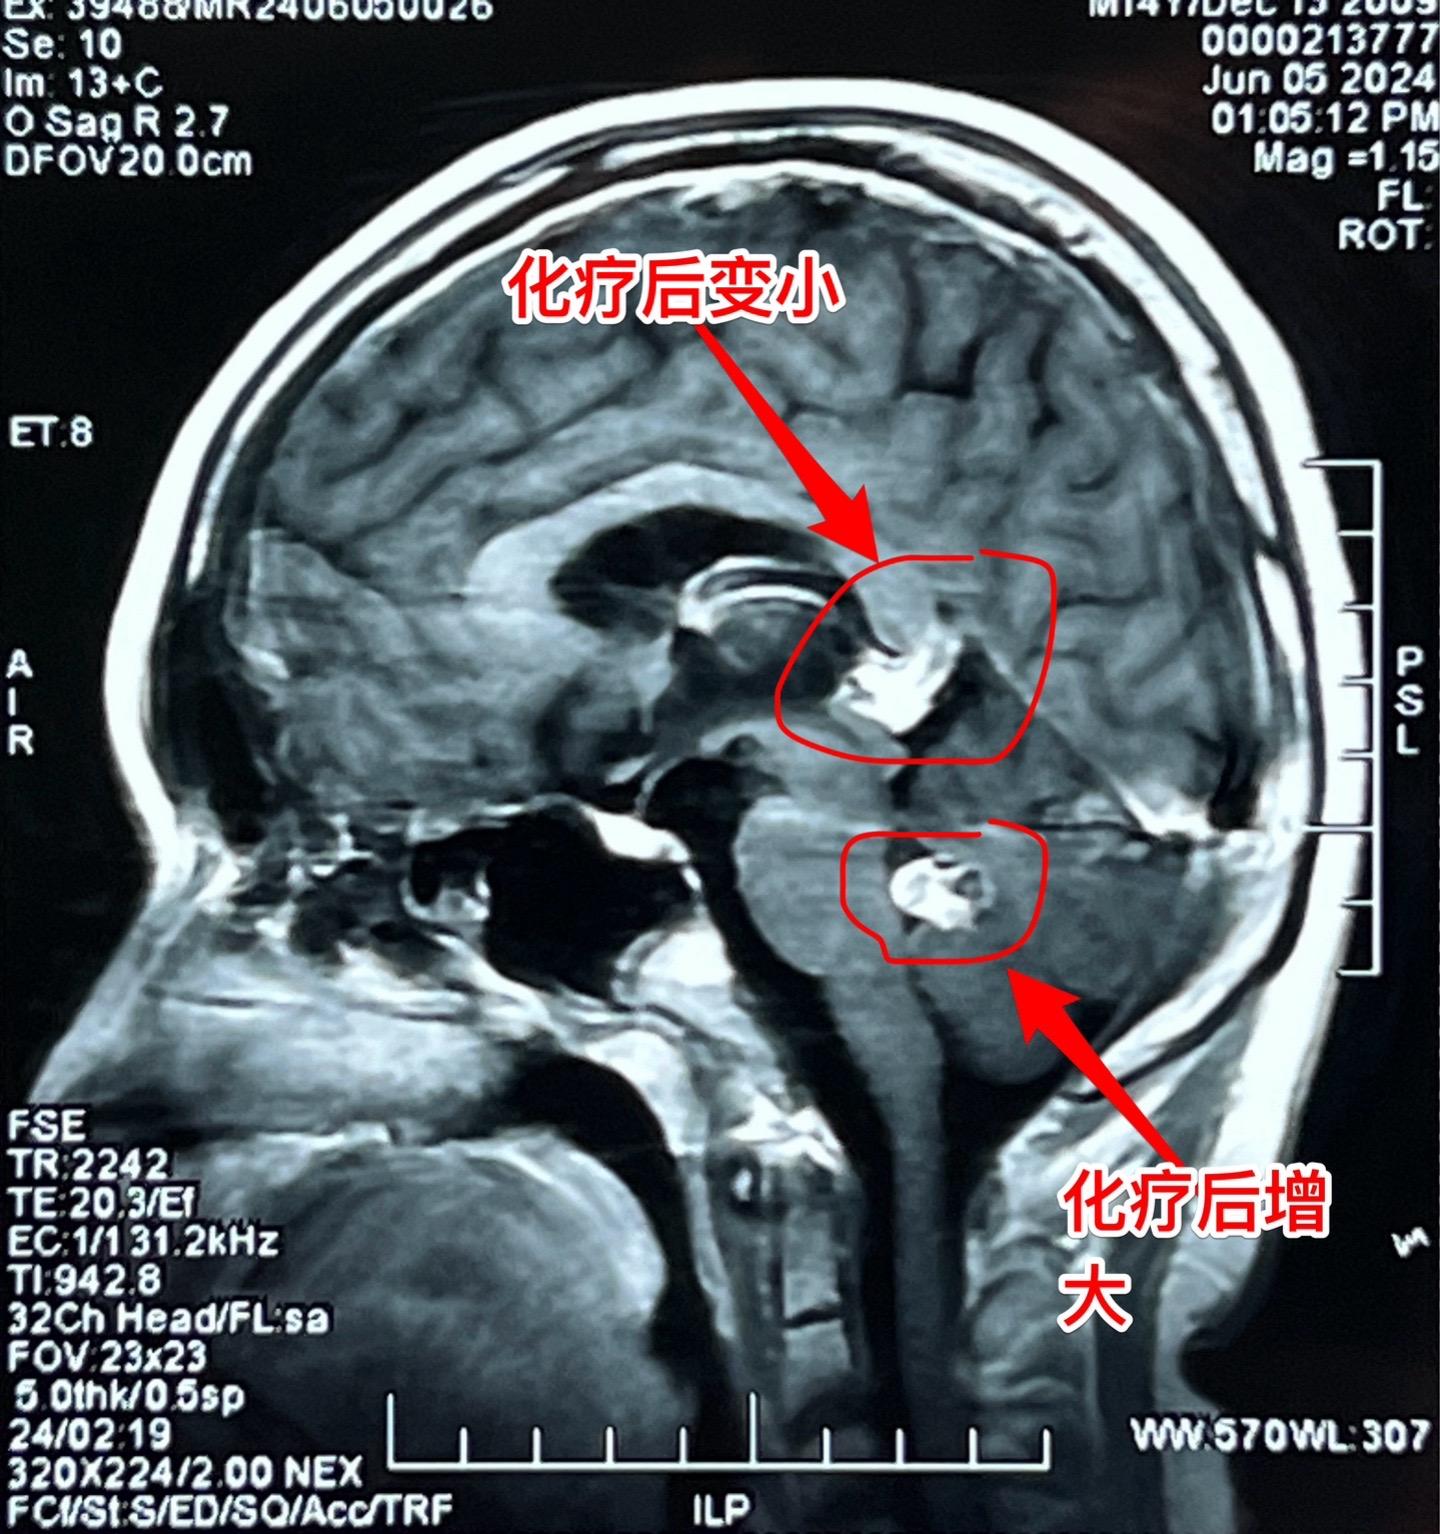

脑部生殖细胞肿瘤一般需要综合治疗。14岁广东省男孩子发现松果体区及第四脑室内多发肿瘤,怀疑是生殖细胞肿瘤。在广州市某医院作了两个疗程的化疗,松果体区的肿瘤明显变小了,但是第四脑室内的肿瘤体积却增大了! 昨天为他作了开颅手术,看见第四脑室内的肿瘤病灶一共有四个,切除了三个,另一个经过化疗后似乎坏死了!等病理报告出来后还需要综合治疗。 恶性的生殖细胞肿瘤一般需要综合治疗,该男孩子病灶有播散转移,应该是恶性肿瘤,为病人祈福🙏。 2024-06-13 10:06